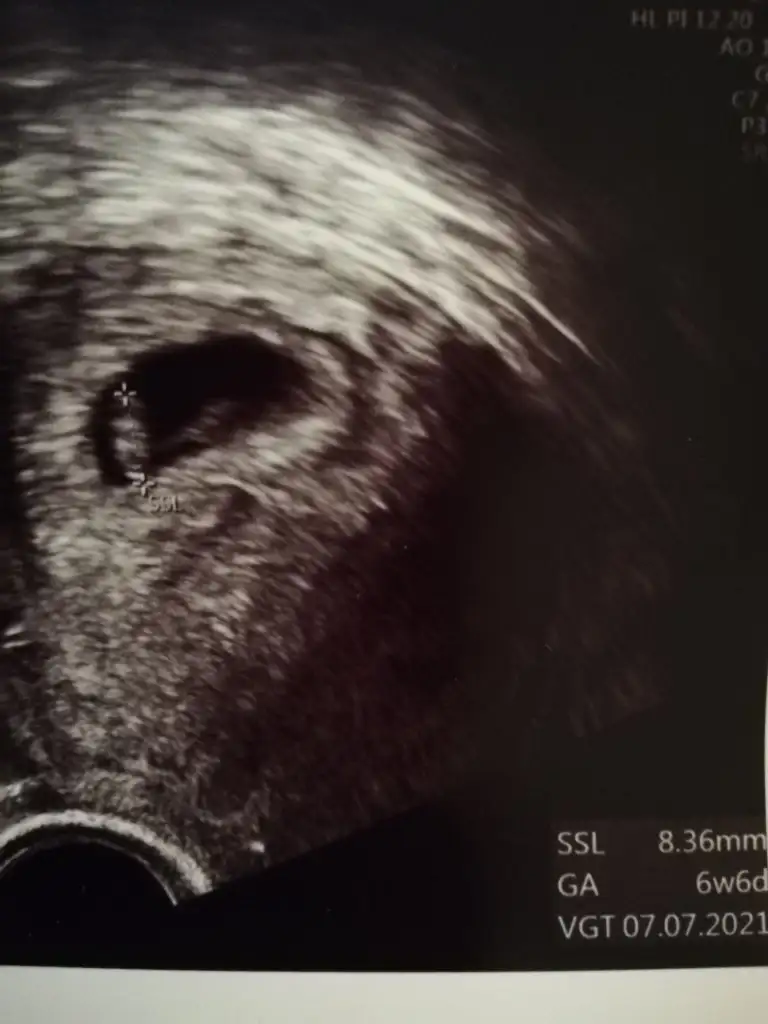

İkra meyra bunada bakabilirmisin bende tahminin tuttu bu da ablamın vajinal çekilmiş 6 haftalıkErkek gibi sanki emin olamadım 12-13 hafta olursa paylasin

Kız görünüyor tabi en iyi 11 12 13 haftalar olmalıİkra meyra bunada bakabilirmisin bende tahminin tuttu bu da ablamın vajinal çekilmiş 6 haftalık